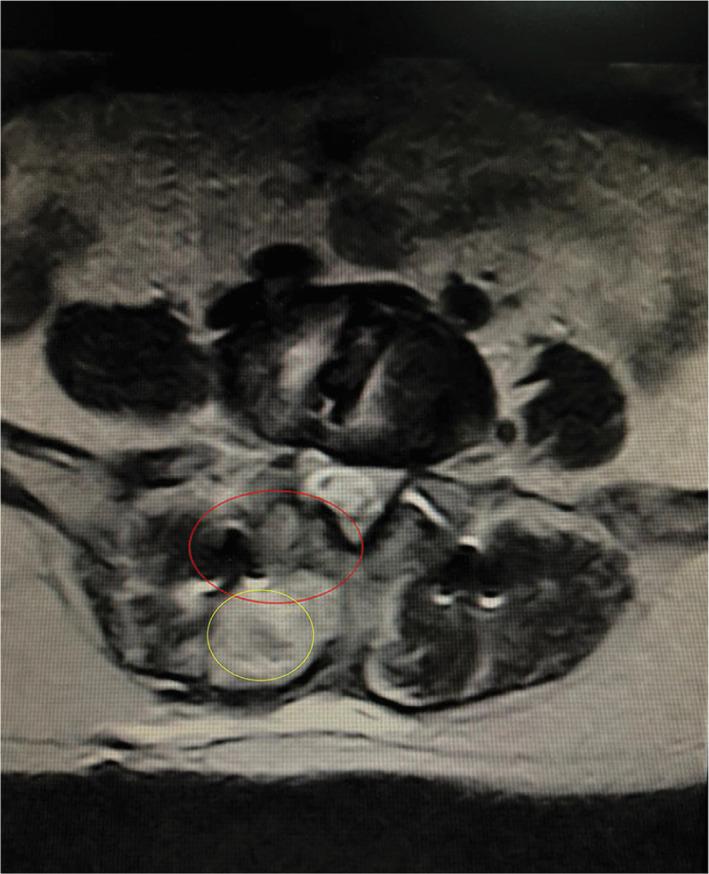

The OLIF and MI-TLIF groups comprised 36 patients (age, 52.1 ± 7.2 years; 27 women) and 45 patients (age, 48.4 ± 14.4 years; 24 women), respectively. Satisfaction rates at 2 years post procedure exceeded 90% in both groups. The OLIF group had less intraoperative blood loss (140 ± 36 vs 233 ± 62 mL), lower back pain VAS score (2.42 ± 0.81 vs 3.38 ± 0.47), and ODI score (20.47 ± 2.53 vs 27.31 ± 3.71) at 3 months follow-up (with trends toward lower values at 2 years follow-up), but higher leg pain VAS scores at all postoperative time points than the MI-TLIF group (all p < 0.001). ADH, PDH, FD, and FW improved in both groups post-surgery. At the 2 year follow-up, the OLIF group had a higher rate of Bridwell grade-I fusion (100% vs 88.9%, p = 0.046) and lower incidences of cage subsidence (8.33% vs 46.67%, p < 0.001) and retropulsion (0% vs 6.67%, p = 0.046) than the MI-TLIF group.

OLIF 组和 MI-TLIF 组分别包括 36 例患者(年龄 52.1±7.2 岁,27 例女性)和 45 例患者(年龄 48.4±14.4 岁,24 例女性)。两组术后 2 年的满意度均超过 90%。OLIF 组术中出血量较少(140±36 比 233±62 mL),术后 3 个月时腰痛 VAS 评分(2.42±0.81 比 3.38±0.47)和 ODI 评分(20.47±2.53 比 27.31±3.71)较低(术后 2 年呈下降趋势),但术后各时间点腿痛 VAS 评分均高于 MI-TLIF 组(均 p<0.001)。两组术后 ADH、PDH、FD 和 FW 均得到改善。术后 2 年时,OLIF 组 Bridwell 分级融合率较高(100%比 88.9%,p=0.046),cage 下沉率较低(8.33%比 46.67%,p<0.001)和后移率较低(0%比 6.67%,p=0.046)。